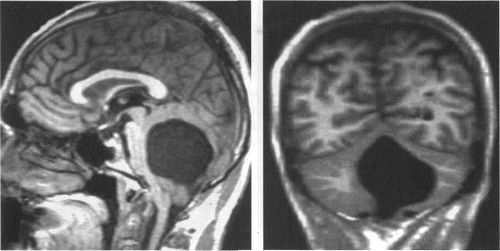

Мал. 3.8. Кістозна трансформація IV шлуночка. МРТ.

а - в режимі Т1, сагітальній площині. IV шлуночок має округлу форму, різко розширено. Черв'як мозочка гипоплазирована, мигдалини розташовуються нижче рівня великого потиличного отвори.

Є висхідний мозжечково-транстенторіальное вклинение з компресією четверохолмной цистерни. Міст і довгастий мозок зміщені вперед.

б - в режимі Т1, коронарна площину. Розширення порожнини IV шлуночка виражено нерівномірно, ліва гемісфер мозочка атрофована в більшій мірі.